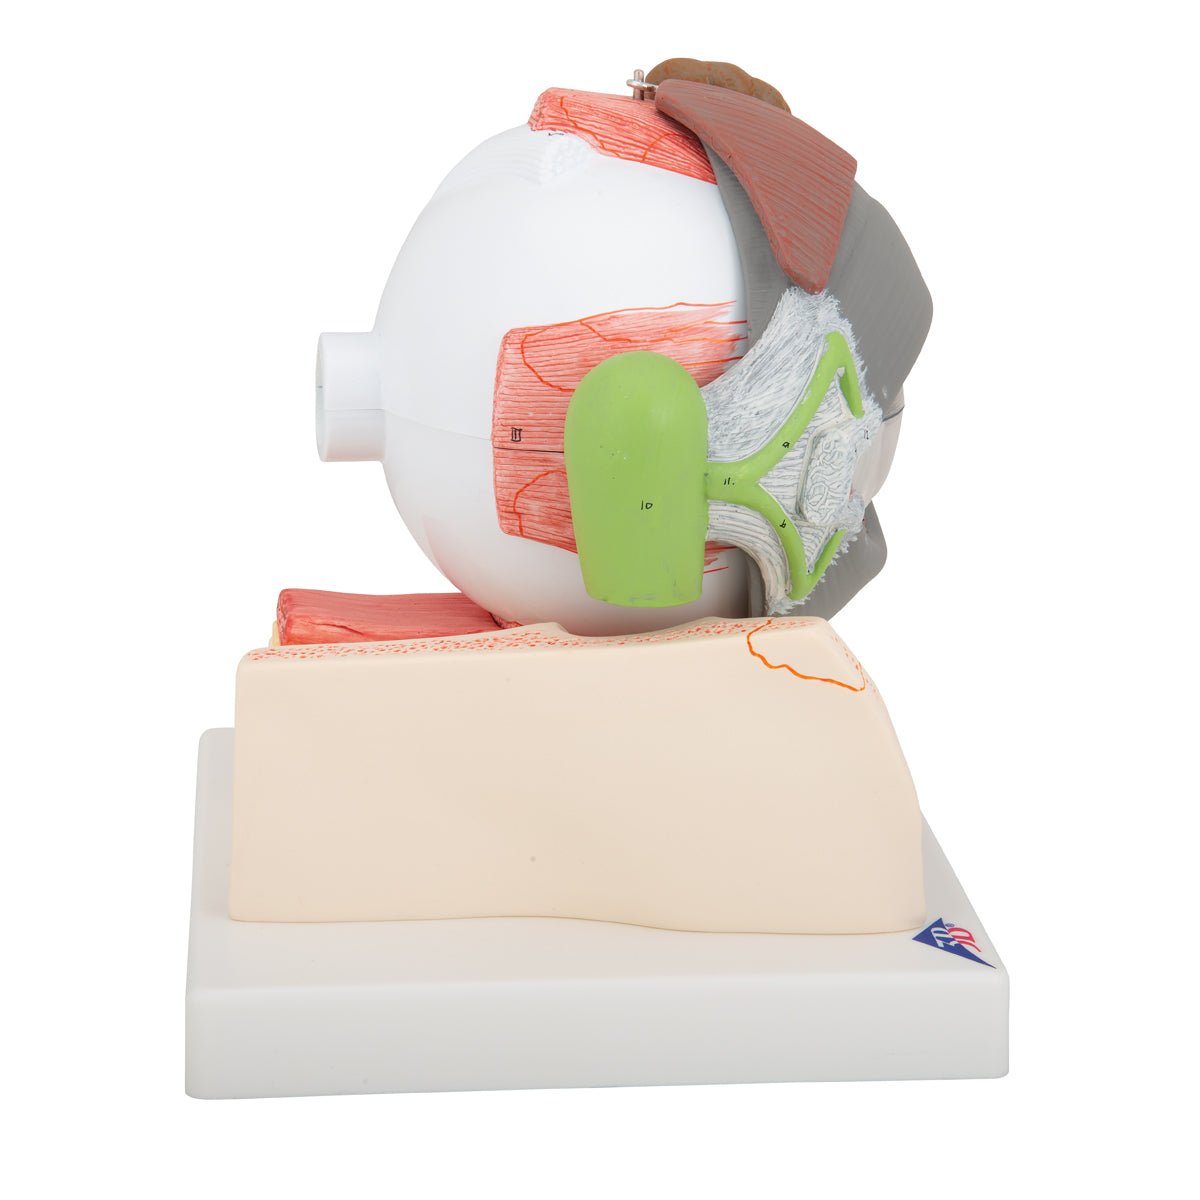

Selling anatomical models is the mainstay of eAnatomi, although we also spend a lot of resources developing our own anatomical materials such as posters. Anatomical models are used for various purposes and can show both defined tissues, organs and organ systems. Are you looking for a simple model of bone tissue or perhaps an advanced torso model based on MRI technology, you can find it all at eanatomi.com.